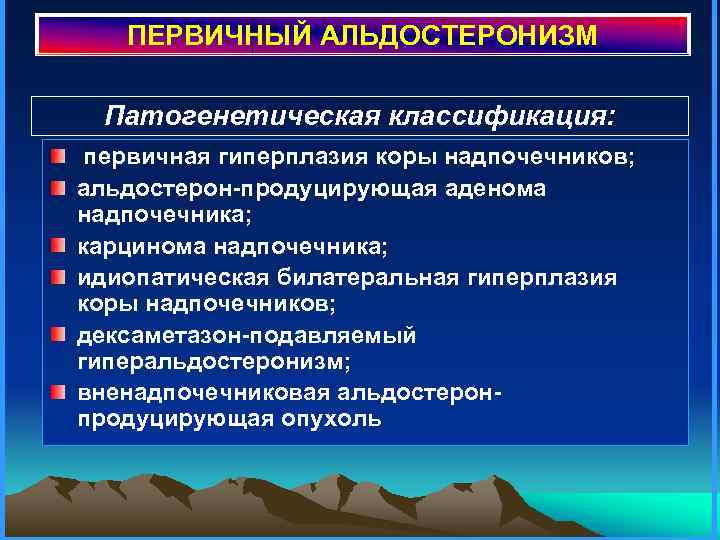

ПЕРВИЧНЫЙ АЛЬДОСТЕРОНИЗМ Патогенетическая классификация: первичная гиперплазия коры надпочечников; альдостерон-продуцирующая аденома надпочечника; карцинома надпочечника; идиопатическая билатеральная гиперплазия коры надпочечников; дексаметазон-подавляемый гиперальдостеронизм; вненадпочечниковая альдостеронпродуцирующая опухоль

ПЕРВИЧНЫЙ АЛЬДОСТЕРОНИЗМ Патогенетическая классификация: первичная гиперплазия коры надпочечников; альдостерон-продуцирующая аденома надпочечника; карцинома надпочечника; идиопатическая билатеральная гиперплазия коры надпочечников; дексаметазон-подавляемый гиперальдостеронизм; вненадпочечниковая альдостеронпродуцирующая опухоль